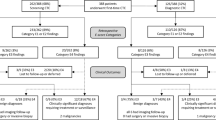

CT colonography requires scanning in two opposing positions, typically in supine and prone. Alternatively, patients with large body mass index (BMI) ≥ 30 may be scanned in the right and left lateral decubitus positions. Therefore, the CTC dose report usually includes two series each with CTDIvol and DLP. Individual DLPs are added together and then converted to an effective dose presented in mSv. The total DLP is multiplied by a conversion factor (k) which is determined by the patient size and the part of the body scanned. Since CTC occurs in the abdomen and pelvis, a conversion factor of 0.015 is employed to obtain the effective dose (Fig. 4) [52]. Flicek et al. were able to reduce radiation dose for CTC by using an effective tube current of 50 mAs in the supine position and decreasing the effective tube current to 25 mAs in the prone position. This strategy results in a low CTC effective dose of about 3 mSv or less which is at least 50% less than previously reported CTC dosage [53]. An effective dose of 3 mSv is also equivalent to the annual background dose that each of us is typically exposed to.

Methods to decrease CT colonography radiation dose

There are multiple strategies currently available to assist in lowering CT radiation dose. Referring providers should assure that there is clear indication for performing CTC. The joint guideline from the American Cancer Society, the US Multi-Society Task Force on Colorectal Cancer, and the American College of Radiology include CT colonography as an indicated test for colorectal cancer screening every 5 years and is an exam that can detect both the malignancy and the precursor polyp [3]. According to the joint practice parameters from the American College of Radiology, the Society of Abdominal Radiology, and the Society of Computed Body Tomography and Magnetic Resonance, indications for CTC include colorectal cancer screening, surveillance, and diagnosis [54]. CTC may also be performed following incomplete colonoscopy and for characterization of colorectal lesions that are indeterminate on optical colonoscopy. CTC is indicated for patients who may be at increased risk for complications during optical colonoscopy (e.g., advanced age, anticoagulant therapy, sedation risk, and prior incomplete colonoscopy) and to follow up patients with a colonic stoma or after colectomy. CTC may also be performed prior to laparoscopic surgery for colorectal cancer in order to accurately localize the tumor or to search for synchronous lesions.

Communication between referring physicians and radiologists can help assure that as many of these strategies are employed as possible when sending patients to imaging centers performing CT colonography. Appropriate centering of the patient in the middle of the scanner gantry is relatively simple to implement to lower radiation dose. Decreasing tube current and/or voltage and use of automatic dose modulation can help lower radiation dose significantly. Iterative reconstruction techniques should be incorporated in CT colonography protocols whenever possible to maximize radiation dose reduction.

Positioning the patient close to the center of the CT gantry helps to optimize image quality and permits the best use of automatic dose modulation. If a patient is not centered correctly on the scanner table, this can result in an unnecessary increase in radiation dose. Habibzadeh et al. found that even a small amount of miscentering of 2.2 cm on a 64-slice CT scanner resulted in an increase of approximately 23% in patient dose with images that were slightly noisier [55]. Proper training of technologists in the use of laser guides is needed in order to help correctly position the patient in the isocenter of the scanner gantry.

Lowering tube current is one of the most common techniques employed to reduce radiation dose. There is a linear correlation between the tube milliampere-seconds (mAs) and radiation dose so that as the mAs is reduced, there is a concurrent proportionate decrease in radiation dose [56]. Typically, low-dose CTC protocols employ effective mAs of 25 to 50. However, image noise increases significantly as the mAs decreases. We are fortunate since detection of intraluminal masses depends on the high contrast between the soft tissue density of polyps and the gas density of carbon dioxide or room air in the lumen. Vogt et al. evaluated 115 patients with 150 colorectal lesions using an ultra-low-dose CTC protocol with 10 mAs [57]. Results showed that the sensitivity and the specificity for detection of polyps 5 mm or larger were 94% and 84%, respectively. For adenomatous lesions larger than 5 mm, sensitivity was 94%, and specificity was 92%. The calculated effective radiation dose was very low and ranged between 0.75 and 1.25 mSv. In a study by Iannaccone et al., 88 patients underwent ultra-low-dose CTC with 10 mAs and sensitivities for detection of polyps 6 mm in diameter or larger were comparable for CT colonography and initial colonoscopy at 86 and 84%, respectively [58]. Ginsburg et al. evaluated 96 patients using 15 or 30 mAs on CTC and found that radiation dose could be reduced by 40 and 70% for overweight and normal body mass index (BMI)-patients, respectively [59]. With large reductions in mAs, three-dimensional images may contain artifacts or minor wall irregularities which may be distracting although smoothing filters can be applied. The use of low mAs technique combined with iterative reconstruction has allowed for improved image quality with significant dose reduction. Readers of low-dose CTC scans will find that extracolonic findings may be more difficult to identify or characterize although this may be offset by using thicker slices or iterative reconstruction.

Additional dose reduction may be achieved with the use of automatic dose modulation. Automatic tube current modulation is a technique where the user determines the preferred image quality, and then the scanner automatically selects the mAs. The tube current is then adjusted during the scan according to the size and density of the part of the body examined also taking into consideration the scan plane. Transverse or longitudinal modulation is determined by referring to the scout images. Both types of modulation may be combined with an angular modulation into a three-dimensional automatic dose modulation which is also termed automatic exposure control (AEC) [60]. The majority of body CT scans is performed currently with the use of AEC. Noisier images are acceptable for many CTC readers given the focus on the high contrast soft tissue–gas interface allowing the ability for significantly higher dose savings than in most other CT exams.

There is increasing use of tube voltage reduction as an effective method to decrease radiation dose for CTC. An exponential correlation occurs between tube voltage and radiation dose so that as peak kilovoltage (kVp) decreases, there is an approximate dose reduction multiplied by a power of 2.6 [61]. Although lower kVp images are noisier, there is a relative increase in the attenuation of residual material tagged with oral contrast on CTC since imaging occurs closer to the K-edge of iodine. This means that readers are still able to identify soft tissue polyps located within tagged fluid pools on low kVp CTC images. Iterative reconstruction may be used in conjunction with low kVp images to decrease image noise allowing for additional dose reduction. Patients with a large body habitus may not be able to undergo low kVp CTC since there will be inadequate penetration by low-energy photons and suboptimal image quality [62]. Chang et al. studied 63 patients who underwent supine (120 kVp) and prone (100 kVp) CTC [63]. A reduction from 120 to 100 kVp resulted in a 20% decrease in CDI vol and a 16% decrease in DLP. Image noise increased by 32%, but there was only a slight decrease in three-dimensional image qualities. In a phantom study by Shin et al., an even lower tube voltage of 80 kVp was employed resulting in a very low effective radiation dose on only 0.166 mSv [64]. However, there was a significant increase in image noise and a decrease in polyp detection sensitivity. Excellent polyp detection sensitivity was achieved by using iterative reconstruction with the 80 kVp scans which were similar to 100 or 120 kVp scans. It is expected that there will be continued dose reduction for clinical CTC examinations to sub-mSv levels.

Until recently filtered back projection (FBP) was the primary reconstruction algorithm used for CT images. However, limitations of FBP include noise and artifacts, and with current increased computing power, iterative reconstruction is now used. Typically, iterative algorithms are employed in conjunction with FBP and allow decreased image noise on low-radiation dose CT images. All major CT manufacturers offer versions of iterative reconstruction and the latest CTC protocols typically employ a blend of FBP and iterative reconstruction [65]. Flicek et al. performed a study evaluating 18 patients undergoing low-radiation dose CTC using 50 mAs in the supine position and 25 mAs combined with 40% adaptive statistical iterative reconstruction (ASIR) in the prone position [53]. This pilot study showed that CTC radiation dose could be decreased by 50% below previously achieved levels without any significant compromise of image quality when ASIR is used. Similarly in a study of 30 patients by Fletcher et al., comparable image quality for colonic evaluation on CTC was achieved for full-dose and half-dose images reconstructed using iterative reconstruction [66]. A larger study by Nagata et al. evaluated 210 patients and found that supine CTC dose was 1.88 mSv compared to < 0.92 mSv for low-dose prone CTC with comparable image quality for supine FBP images and prone images using iterative reconstruction [67]. This study showed that dose could be lowered even more to up to about 75% without significant degradation of image quality. Other studies have corroborated the finding that significant dose reduction of greater than 50% can currently be achieved for CTC particularly when employing model-based iterative reconstruction (MBIR) without compromise of image quality. (Figs. 5, 6) [68,69,70]. MBIR is more computationally intensive and requires longer reconstruction times although it allows greater noise reduction than other iterative reconstruction algorithms.